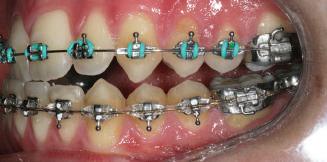

8 Dental Tribune Bulgarian Edition / октомври 2022 г. По време на лечението Фиг. 21 Фиг. 25 Фиг. 30 Фиг. 31 Фиг. 34 Фиг. 38 Фиг. 40 Фиг. 44 Фиг. 48 Фиг. 50 Фиг. 49 Фиг. 46 Фиг. 39 Фиг. 41 Фиг. 45 Фиг. 47 Фиг. 42 Фиг. 43 Фиг. 35 Фиг. 36 Фиг. 37 Фиг. 32 Фиг. 33 Фиг. 26 Фиг. 28 Фиг. 29 Фиг. 27 Фиг. 22 Фиг. 23 Фиг. 24

closed.

21Dental Tribune Bulgarian Edition / октомври 2022 г. ДИАГНОСТИЧНИ РЕЗУЛТАТИ: 1. Възраст на пациента: 21 години 2. Скелетен клас III (ANB 0) 3. Зъбен клас 3 4. Ръбцова захапка във фронта, кръстосана в дисталните участъци 5. Тясна горна челюст 6. Overjet – 0 мм, Overbite – 0 мм 7. Несъответствие на горната с долната средна линия 8. Единични контакти в ЦО 9. Хиподивергентен тип на растеж SN/MP – 33.5 10. Неравен гингивален контур 11. Неравна линия на усмивката 12. Тенденция за рецесии в долен фронт ПРЕПОРЪЧИТЕЛНО ЛЕЧЕНИЕ: Пълно ортодонтско лечение с метални брекети „Алекзандър“ Корекция на клас 3 захапката в областта на кучешките зъби с екстракция на първите пре молари в долна челюст Корекция на кръстосаната захапка в дистални участъци Коригиране на ръбцовата захапка във фронта Подобряване на ОJ и OB на пациента Стрипинг в долен фронт Подреждане на зъбите в горната и долната челюст Професионално хигиенизиране и профилактични дентални прегледи са препоръчителни на всеки 6 месеца. 1-ви месец След 1 месец са залепени брекети в горната челюст – поставена е еластична дъга. 016 NiTi. В долната челюст са елиминирани ротациите, поставена е стоманена дъга. 016SS, закалена с ток, и еластична верижка за затваряне на пространствата. 3-ти месец В долната челюст е поставена трета дъга – 17 x 25 NiTi с къси лигатури и верижка

В горната челюст се затварят пространствата с дъга .016SS и верижка. 5-и месец На 5-ия месец след залепяне на брекетите в долната челюст е поставена стоманена дъга 16 x 22 SS с четвъртито сечение, омега луп и тай бек. В горната челюст е поставена дъга 17 x 25 NiTi. Поради липсата на стабилни оклузални контакти са поставени лингвални верижки в областта на моларите, за да се предотврати нежелана ротация на 7-ите зъби. 6-и месец На 6-ия месец от началото на лечението са екстрахирани долните първи премолари, поставена е дъга 16 x 22 SS със затваряща чупка teardrop. Чупката се активира всеки месец по 1 мм с чинч-бек. клиничен случай | ортодонтия СТЪПКИ НА ЛЕЧЕНИЕТО Начало на лечението Лечението започва с поставяне на апарат за бърза експанзия в горната челюст. През първия месец от лечението са направени 24 оборота на апарата за експанзия. Залепени са брекети в долната челюст, поставена е дъга 17x25 CuNiTi, като са предпи сани клас 3 ластици (1/4”,4 1/2 oz) по време на сън, за да се осигури контрол върху торка на долните резци. Фиг. 2а Фиг. 3a Фиг. 4a Фиг. 3b Фиг. 4b Фиг. 3c Фиг. 4c Фиг. 3d Фиг. 4d Фиг. 3e Фиг. 4e Фиг. 5a Фиг. 5b Фиг. 5c Фиг. 5d Фиг. 5e Фиг. 6a Фиг. 6b Фиг. 6c Фиг. 6d Фиг. 6e Фиг. 7a Фиг. 7b Фиг. 7c Фиг. 7d Фиг. 7e Фиг. 2b Фиг. 2c Фиг. 2d